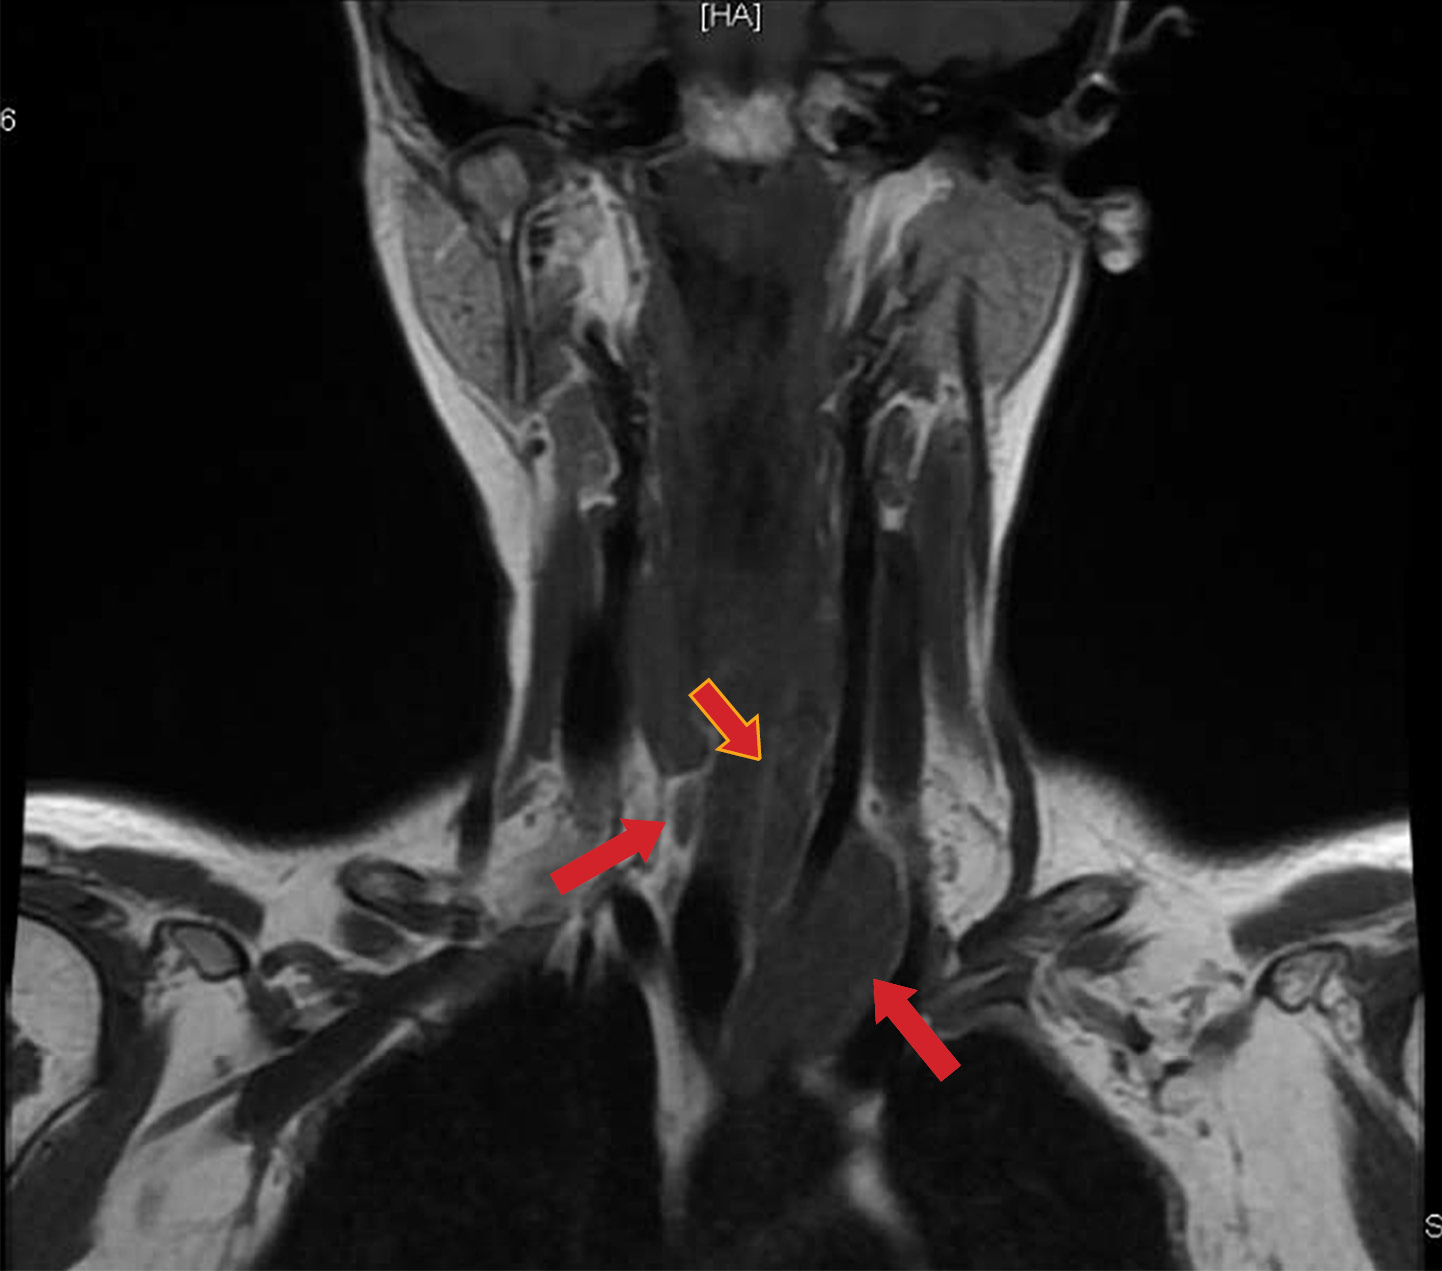

Рисунок 1. Мультиспиральная компьютерная томография шеи и верхнего средостения пациентки С. с контрастированием (белой стрелкой указана деформация правой ключицы, красной стрелкой — образование левой околощитовидной железы).

1. Рисунок 1. Мультиспиральная компьютерная томография шеи и верхнего средостения пациентки С. с контрастированием (белой стрелкой указана деформация правой ключицы, красной стрелкой — образование левой околощитовидной железы). | |